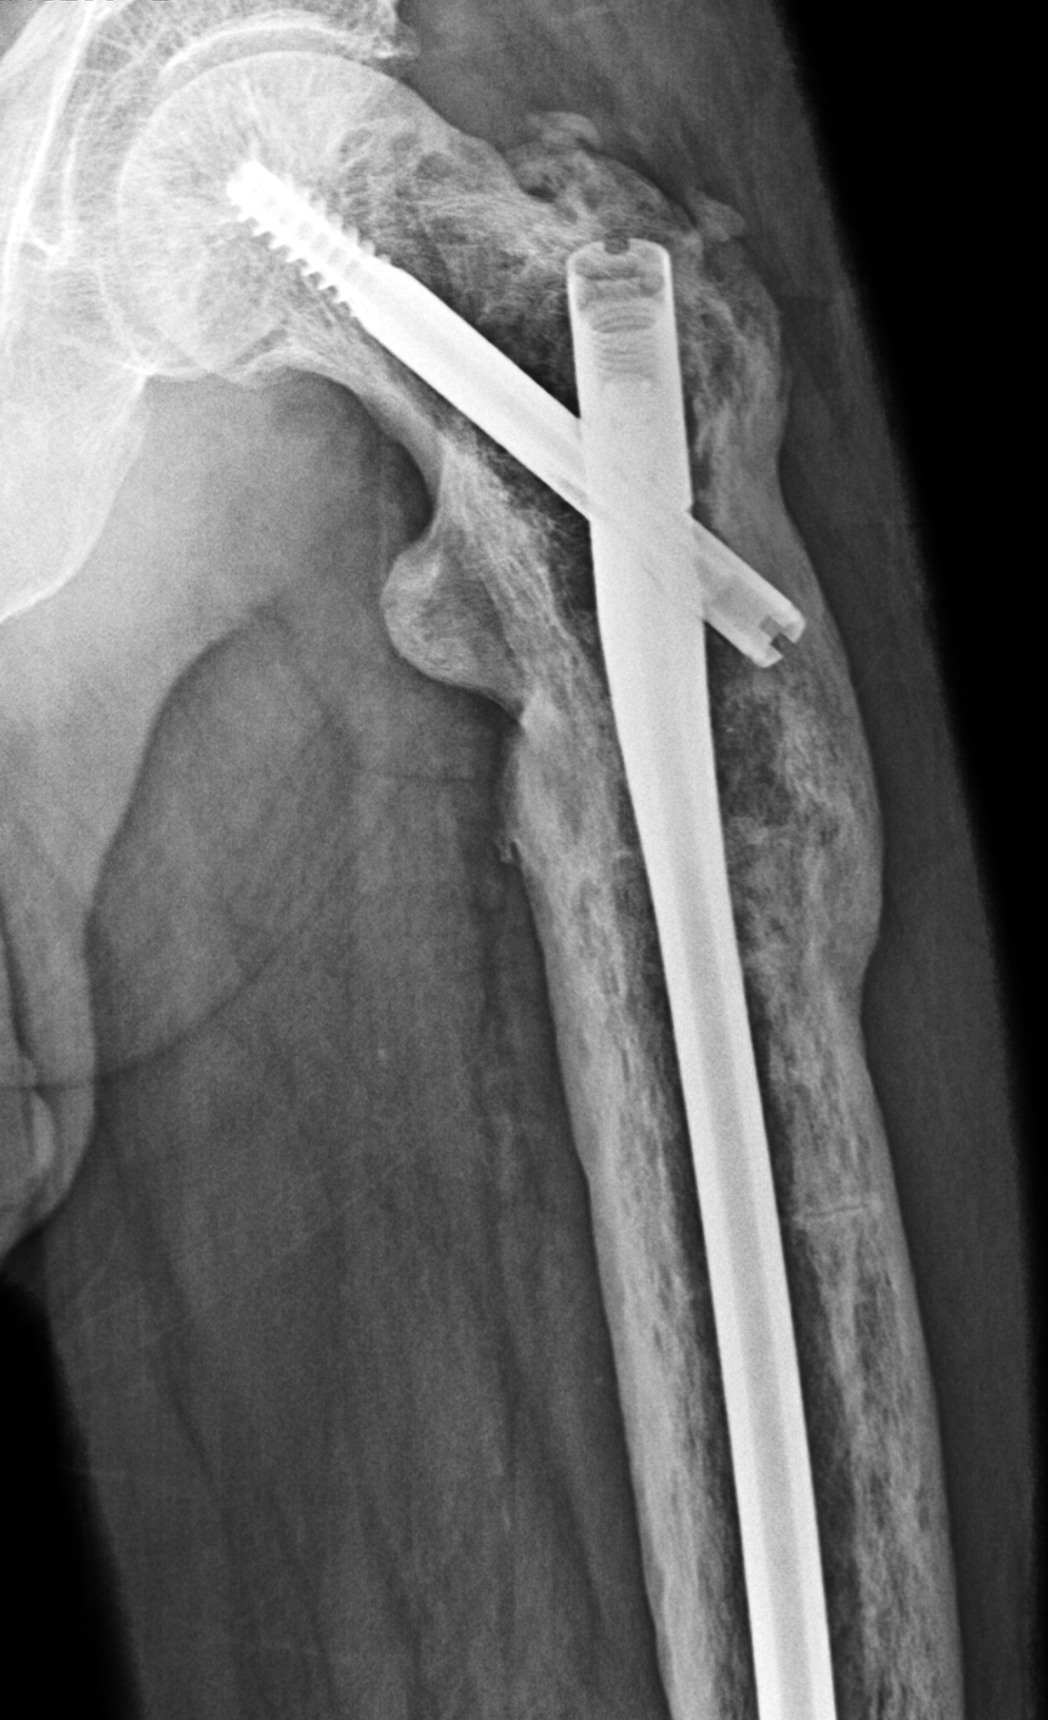

Figure 7: Mixed phase Paget disease of the proximal femur with a developing pathologic fracture. (7A) T1-weighted and (7B) STIR coronal images of the hip show typical MRI pattern 2 findings of Paget disease. Note the mild varus bowing of the femoral neck (red arrows), as well as the developing incomplete, transverse fracture through the lateral cortex (yellow arrows) representing a Pagetic “banana” fracture. (7C) AP radiograph following intramedullary nailing demonstrates fracture healing.

Figure 8: Mixed phase Paget disease in the distal humerus with atypical marrow replacement. (8A) AP and (8B) lateral elbow radiographs show classic findings of Paget disease in the distal humerus, including osseous enlargement, particularly of the medial epicondyle, with associated cortical and trabecular thickening. (8C) T1-weighted and (8D) STIR coronal images show diffusely abnormal marrow signal intensity in the medial humeral epicondyle (asterisks), hypointense compared to skeletal muscle on the T1-weighted sequence and uniformly hyperintense on the STIR sequence. This pattern of marrow replacement is atypical in uncomplicated Paget disease and prompted biopsy, which confirmed the diagnosis. Despite the marrow findings, the radiographic features in addition to the lack of osseous destruction and soft-tissue mass suggest uncomplicated Paget disease and fibrovascular changes. Short interval follow-up to document stability may obviate the need for biopsy in similar cases.